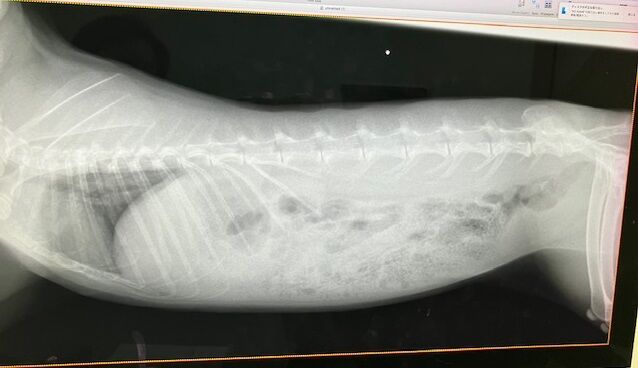

術前検査のレントゲン

特に問題ありません。

※クリックで拡大見れます。